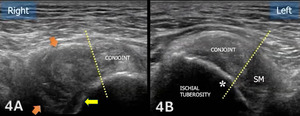

The starting point for examining the proximal hamstring tendon and muscle is at the osseous landmark – the ischial tuberosity.12,13,17–19 The ischial tuberosity can almost always be palpated, giving the examiner a perfect location to begin their scan. The proximal hamstring can be scanned in both the long axis (LAX) and the short axis (SAX). In the LAX view, depending on the probe width and size, one should start proximally to visualize the hyperechoic reflection of the bony cortex of the ischial tuberosity, with its large acoustic shadow underneath. In LAX, the proximal hamstring tendon fibers of the long head of the biceps femoris and the semitendinosus conjoint tendon should be easily seen coming off the attachment of the ischial tuberosity with a clear hyperechoic fibrillar structure running distally from the insertion site on the anterior lateral origin of the ischial tuberosity. The semitendinosus fibers can be easily seen as they reach the ischial tuberosity directly. Lateral to the hamstring muscle complex, the sonographer will see the sciatic nerve that appears as a fascicular, flattened structure that descends between and deep to the long head of the biceps femoris and semimembranosus tendon.1 The probe can be turned 90 degrees for viewing in the SAX. If the probe is moved slightly distally in the SAX view, the biceps femoris will appear as a triangular shape. As the examiner moves distally along the biceps muscle belly, the size will decrease until it appears to disappear. In both views, some toggling may be required to reduce anisotropy.